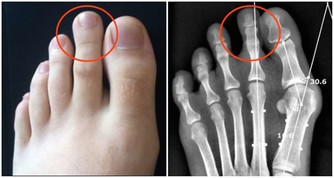

幸運的是,維生素B12缺乏症一旦被識別和診斷,就可以輕鬆解決。這裡還有一些跡象和症狀,可以幫助確定此情況的存在。甚至有些也可以通過檢查眼睛來看到。

根據醫學專家的說法,眼睛的輕微發黃可能表明這個情況。眼抽搐和眼瞼痙攣也是有助於查明維生素B12缺乏症的跡象。在極少數情況下,可能導致視力喪失的視神經損傷可能發生。

如果這些跡像有一天對你明顯,你需要馬上去看醫生。維生素B12缺乏可以很容易地逆轉與靜脈維生素B12治療和補充。體徵和症狀可能突然或逐漸出現,因此最好定期檢查。